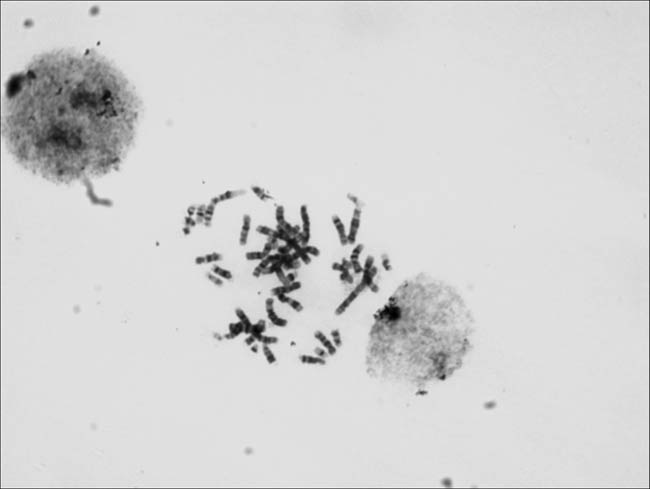

Should be the requirements of our customers, the Tucson special will be two high sensitivity CCD (TCC-1.4HICE (black and white) /TCC-1.4CHICE (color), in the biological study of microscopic images taken by chromosome released, welcome everyone to share.

Taken by Tucsen TCC-1.4H